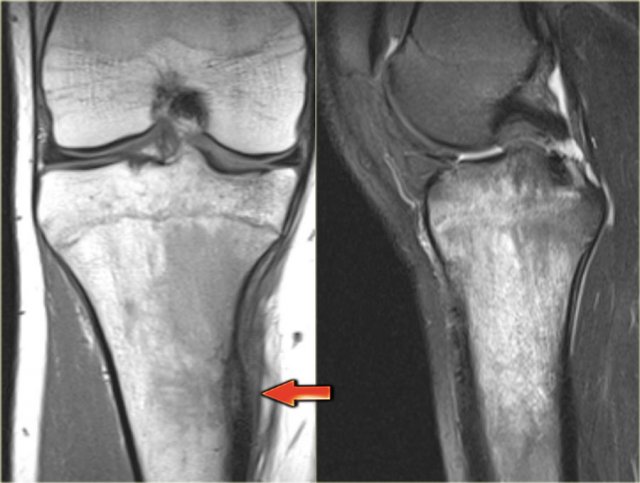

X-ray an CT-image of a typical osteoid osteoma in the proximal tibia.

Notice the sclerotic center within the osteolytic lesion (red arrow).

MR-images of the same patient demonstrate cortical thickening and extensive edema.